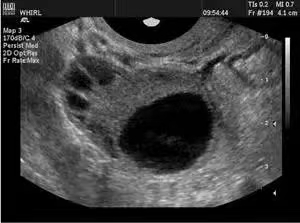

卵巢最主要的功能是产生卵子,卵子在卵泡里和卵泡同步发育,我们通过观察卵泡来推测卵子的发育情况。卵巢的皮质内有多个直径﹤10mm的小卵泡回声,称之为窦卵泡,当窦卵泡直径超过10mm便成为生长卵泡,当生长卵泡继续增大就成为了医生常说的优势卵泡。

通常每月只有一个优势卵泡,当优势卵泡﹥18mm则成为成熟卵泡。而卵泡监测则是在超声介导下对卵泡的直接观察,卵泡监测是一个动态的过程,每周期需要至少3-4次的超声监测。监测卵泡检查虽然看起来比较麻烦,但是评估卵泡最直观的方法,具有重要的临床意义。

对于丈夫精液查正常的,自行监测基础体温1-3个周期仍未受孕的不孕患者,可选择医院就诊B超监测; 对于月经周期长、月经紊乱甚闭经无法推算排卵期的女性,可能存在排卵时间晚甚至无排卵,需医院就诊B超检查排卵情况; 对于多囊卵巢综合征患者,通常出现无排卵或者稀发排卵的表现,受孕几率低,需要调整月经、控制胰岛素抵抗、减重的等治疗措施后,可促排卵后,通过阴道B超监测查看卵泡发育情况,判断是否有成熟卵泡被募集,并由医生指导同房提高受孕几率; 对于卵巢储备不良的患者,可通过B超监测有无排卵,若有排卵,指导同房,精准受孕;卵巢储备明显下降者,B超监测小卵泡的数量,决定是否需要辅助生殖技术助孕; 促排卵周期,卵泡对激素的反应因人而异,部分仅表现为卵巢数目的增大而卵泡大小不增加,测定卵泡个数有助于临床调整用药方案及剂量,获取优质卵泡。 卵泡监测开始时间不定,不同阶段观察要点不同。 月经第3-5天:观察窦卵泡数量(常用于月经失调、卵巢功能减退及试管婴儿需要促排卵患者等); 月经8-10天:常规开始监测卵泡,隔2-3天监测;卵泡﹥15mm时:每天或隔天监测,卵泡18-20mm时,为成熟卵泡,此时可诱导排卵; 整个月经周期,卵泡的生长速度是不一致的:月经周期10天内0.5 -1mm/d,10天后的优势卵泡1-2mm/d,排卵前3天2-3mm/d。 排卵的监测可以有多种方法,包括观察超声、血尿LH峰值、基础体温、宫颈粘液评分等。 超声一般不能观察到成熟卵泡排卵的实况,但可以通过间接征象判断是否已经排卵,这些间接征象包括: ·成熟卵泡消失或者明显缩小 ·卵泡壁不规则、增厚、边缘皱缩,内充满细小弱光点。 ·盆腔少量积液,一般﹤1cm,2-3天消失。 每个月经周期可以分为月经期、卵泡期和黄体期。每个人月经周期可以不一致,但黄体期是固定的14天,所以排卵一般发生在下一次月经来之前的第14天。 总之,卵泡太小、卵泡过大、不排卵、卵泡形态不规则均是卵泡发育异常的超声表现。超声监测排卵简单、可靠、无需做特殊准备。 临床上通过做排卵监测可以评估卵子质量、测量内膜厚度、指导备孕女性更好地备孕。女性两侧卵巢一般是轮流排卵,有时也会出现同一侧连续排卵。对于有一侧输卵管炎症或者输卵管异位妊娠史的女性,可以通过超声监测,指导健侧排卵时同房,增加正常受孕的几率。对于月经不规则、多囊卵巢综合征患者及卵泡发育不良患者,监测排卵对于备孕更有着至关重要的作用。 怀孕是一件幸福的事情,同时又是一个复杂的过程,合理进行排卵监测可使备孕过程“事半功倍”。但除了监测排卵,备孕路上还有各种学问,规律性生活未避孕未孕1年即诊断为不孕症,应积极寻求生殖专科医生的帮助,临沂市妇幼保健院生殖医学科祝广大备孕女性朋友好“孕”连连。 【妇幼健康科普,传播健康知识】